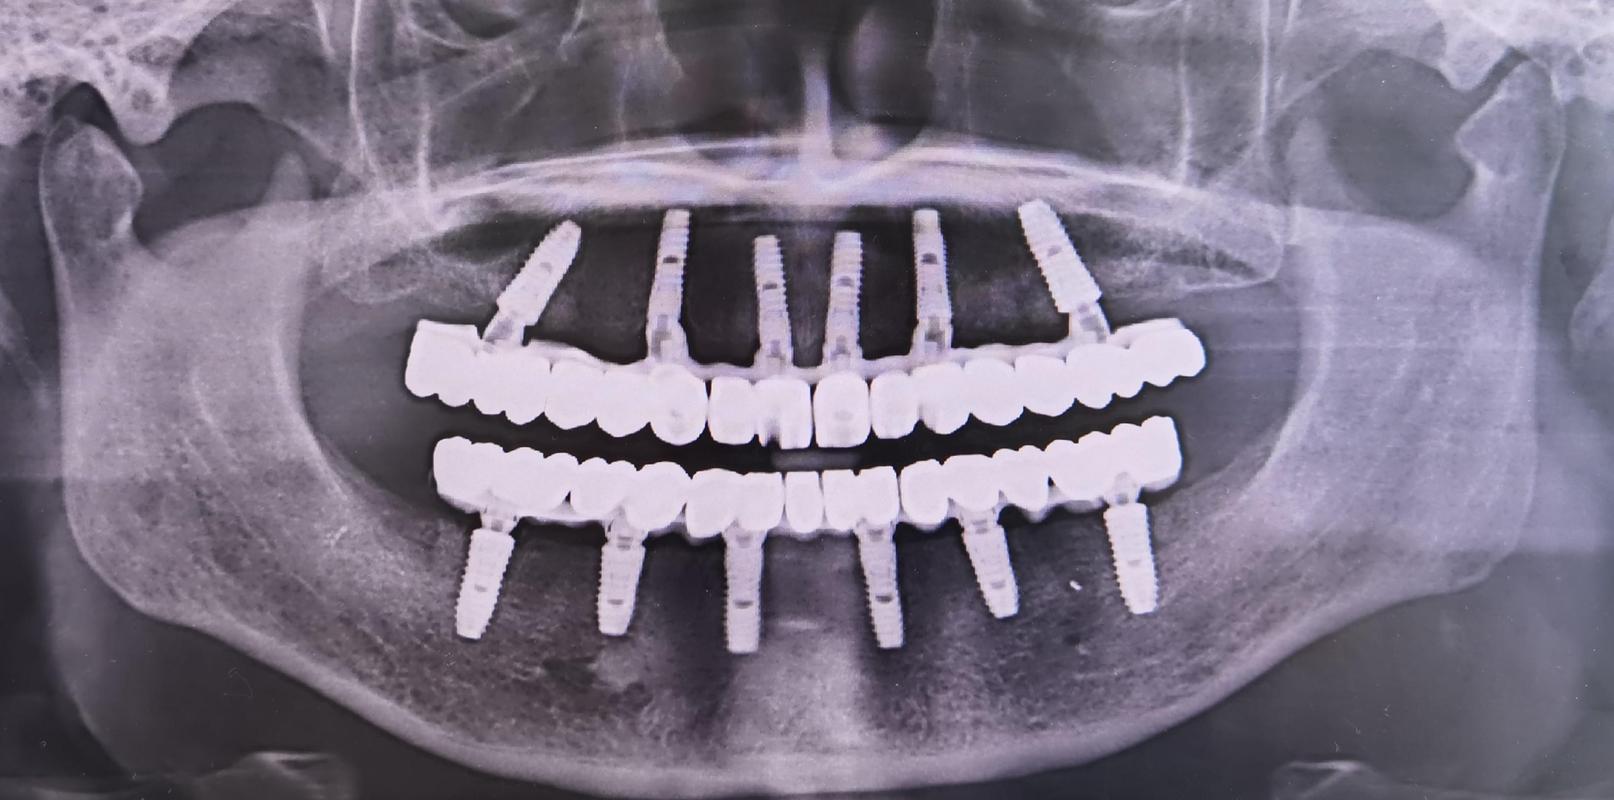

数字化种植技术是当前的核心优势,通过CBCT(锥形束CT)扫描获取口腔三维数据,结合3D打印技术制作种植导板,能精准规划种植体的位置、角度和深度,避免损伤神经血管,南京医科大学附属口腔医院引进的动态导航种植系统,可将误差控制在0.1毫米以内,尤其适合骨量不足或解剖结构复杂的患者。

即刻种植与即刻负重技术广泛应用,对于符合条件的患者(如牙槽骨条件良好、无严重炎症),可实现“即拔即种”,甚至当天植入种植体后安装临时牙冠,缩短治疗周期至2-3个月,传统种植则需要3-6个月,苏州大学附属第一口腔医院开展的“All-on-4”半口/全口即刻负重技术,仅需4颗种植体即可支撑半口牙桥,为半口缺牙患者提供了高效解决方案。